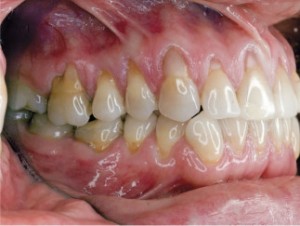

| Pacjentka w wieku 40 lat przed leczeniem. Mnogie (wysokie i szerokie) recesje dziąsła, ryc. 1 | Pacjentka w wieku 40 lat przed leczeniem. Mnogie (wysokie i szerokie) recesje dziąsła, ryc. 2 | |